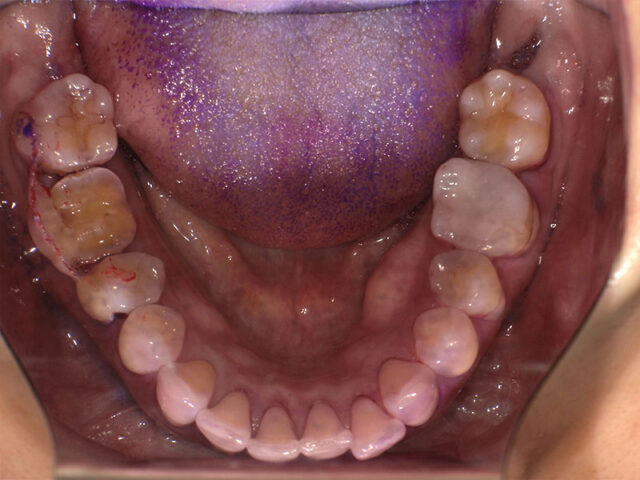

口腔内写真(術前・移植前)